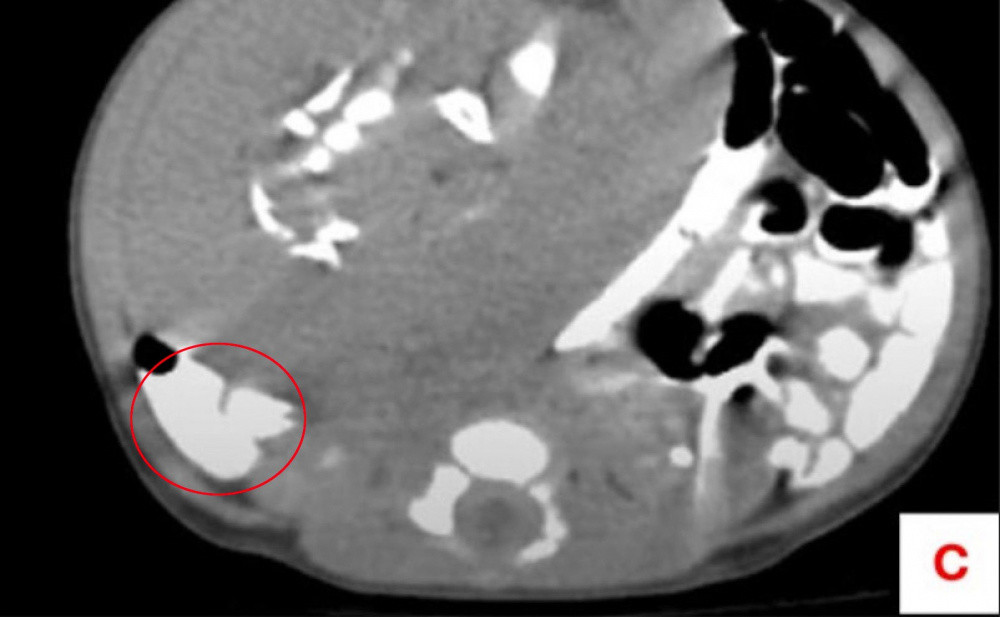

Египетте жаңы төрөлгөн ымыркайдын ичинен толук калыптана элек паразит түйүлдүк аныкталып, дарыгерлер операция жолу менен аны алып чыгышты. Ымыркай төрөттөн 11 күн өткөн соң курсагы чоңоюп кеткендиктен ооруканага жеткирилген. Бул тууралуу чет элдик басылмалар жазышты.

Маалым болгондой, текшерүү убагында анын курсагында 8х6 сантиметрдей белгисиз масса бар экендигин көрсөткөн. Паразит түйүлдүк ымыркайдын кан тамыры аркылуу азыктанганы аныкталган.

Хирургдар боордун жанынан табылган бул паразит түйүлдүктү ийгиликтүү алып чыгышкан. Медициналык изилдөөдө анын ичинде май ткандары, эки бутка окшош мүчө, териси жана ичеги сыяктуу толук калыптанган бөлүктөр болгондугу аныкталды.